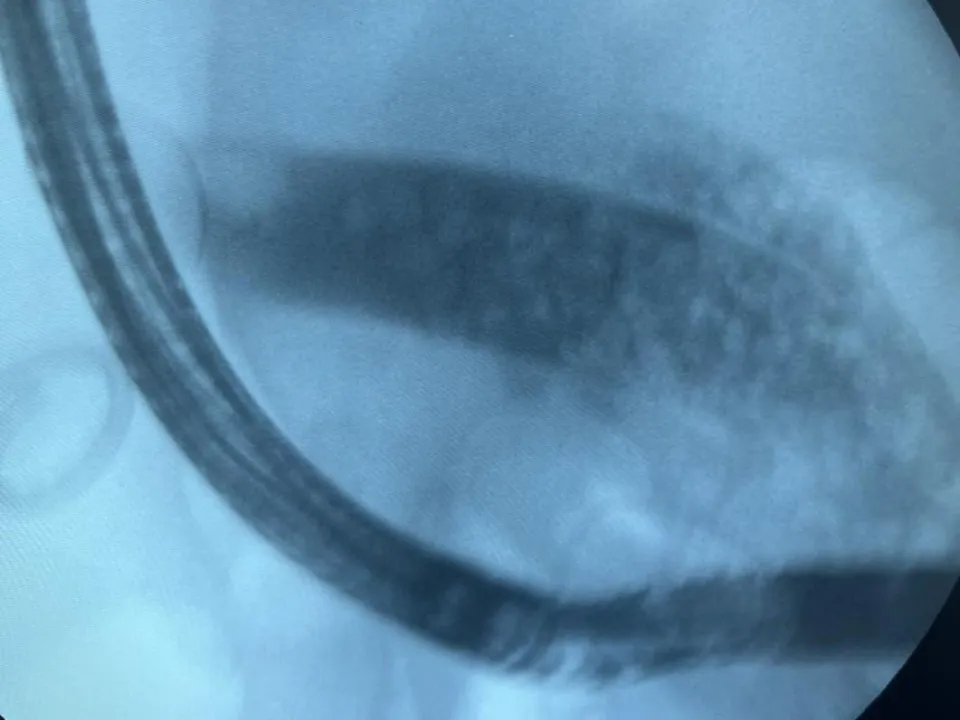

Завотделением эндоскопии Агарон Айвазян подробно описал ход вмешательства. Он сообщил, что врачи выполнили рассечение большого дуоденального соска, сфинктеротомию, затем с помощью специального баллонного инструмента расширили устье желчного протока до необходимых размеров.

После проведения этих этапов желчь и камни начали активно поступать в просвет кишки. Крупные камни были перемещены в кишечник специальной корзиной, откуда в дальнейшем они вышли естественным путем. В общей сложность из организма женщины было удалено более 50 камней. При контрольном осмотре протоков камней обнаружено не было.